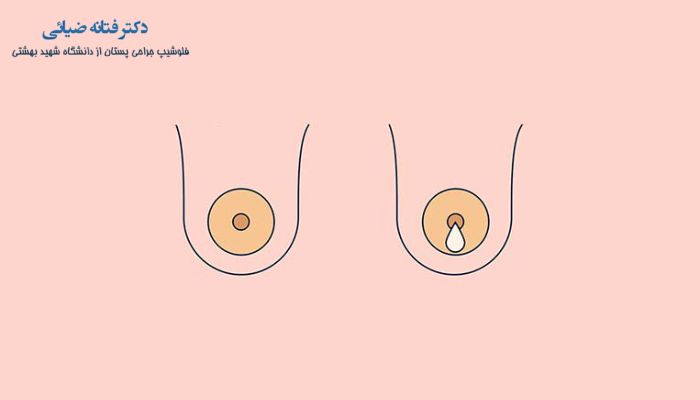

ترشحات نوک پستان، غرطبیعی هستند اگر ویژگی های زیر را داشته باشند:

- ترشح خونی از نوک سینه: ترشحات خونی تقریبا همیشه نگران کننده است.

- فقط از یک سینه خارج می شود.

- خود به خود نشت می کند (بدون اینکه نوک سینه خود را لمس کرده یا فشار دهید).

- با علائمی مانند درد سینه، قرمزی، تورم یا تغییرات در نوک پستان همراه است.